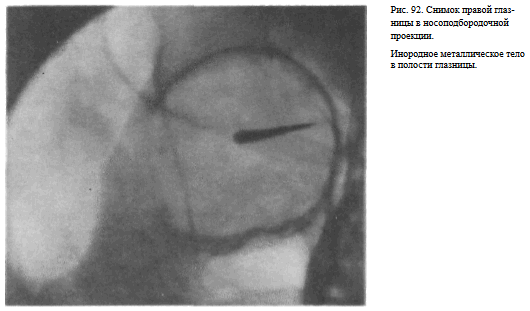

На прицельном снимке каждой из глазниц в этой же проекции, как правило, небольшие изменения структуры стенок, а также мелкие инородные тела глаза видны лучше. Такие снимки широко используют в офтальмологической практике (рис. 92).

В этой же укладке может быть выполнен снимок одной (правой или левой) глазницы. В таких случаях центр снимаемой глазницы соответствует центру кассеты, и на него отвесно направляют пучок излучения, используя тубус или диафрагмирование пучка излучения с помощью щелевой диафрагмы. Фокусное расстояние—100 см (рис. 88).